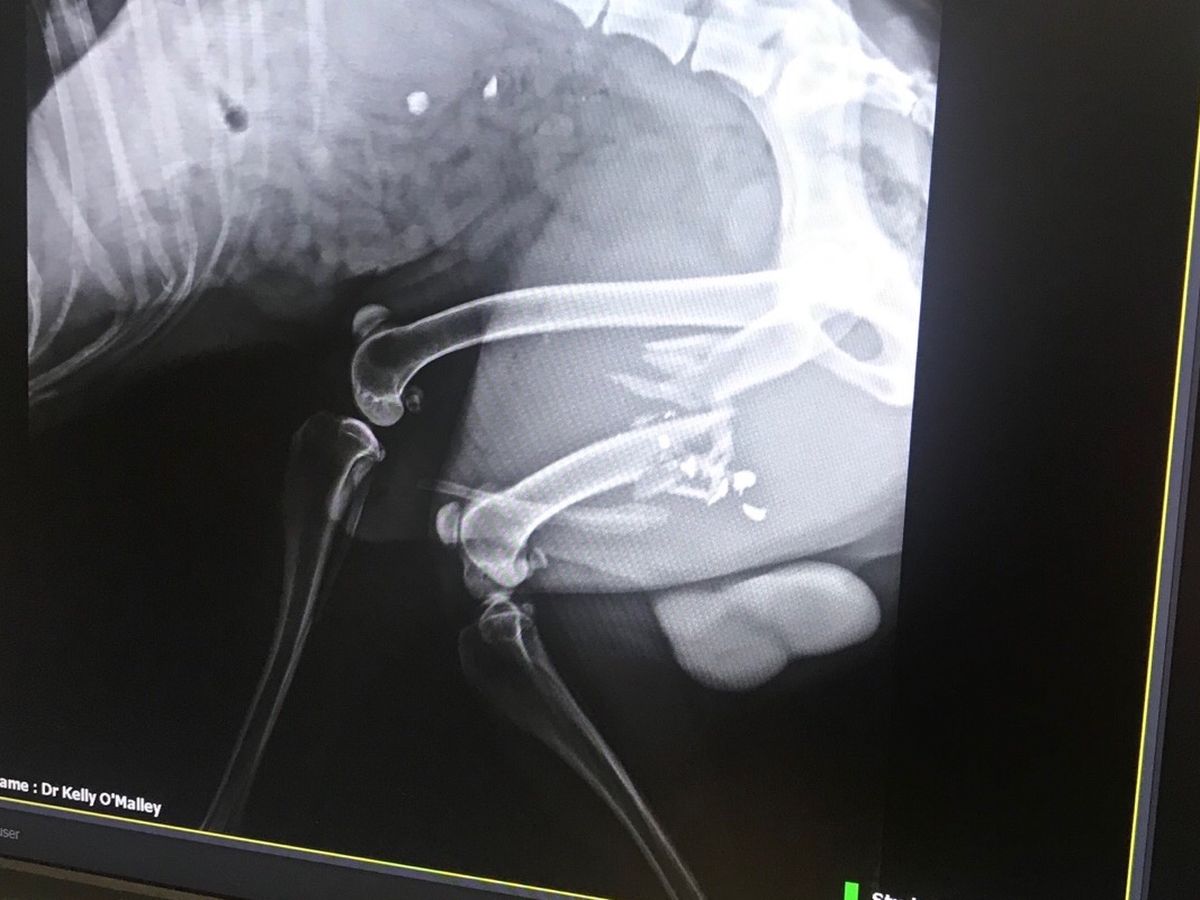

Saturday morning he went for a run and found himself in the sights of a high powered rifle. For some reason, I don’t know, someone shot him. He’s never been aggressive, he doesn’t go near livestock, and is always friendly to other people and pets. He couldn’t have been far from home because he drug himself back. We thought he had been hit by a car and rushed him to the emergency vet where they found the 22 hollow point bullet that shattered his femur. There was nothing they could do there so now we had to wait to see our normal vet. Dr. Lutz Harfs at Animal Medical Services told us that the only way to repair this was to surgically put a steal plate in and we needed to go see a specialist in Spokane because no one in town did this type of operation. Amputation is not a good option because he is such a large dog and large dogs use their hind legs to get up, down, and all around. It could really affect his life expectancy....